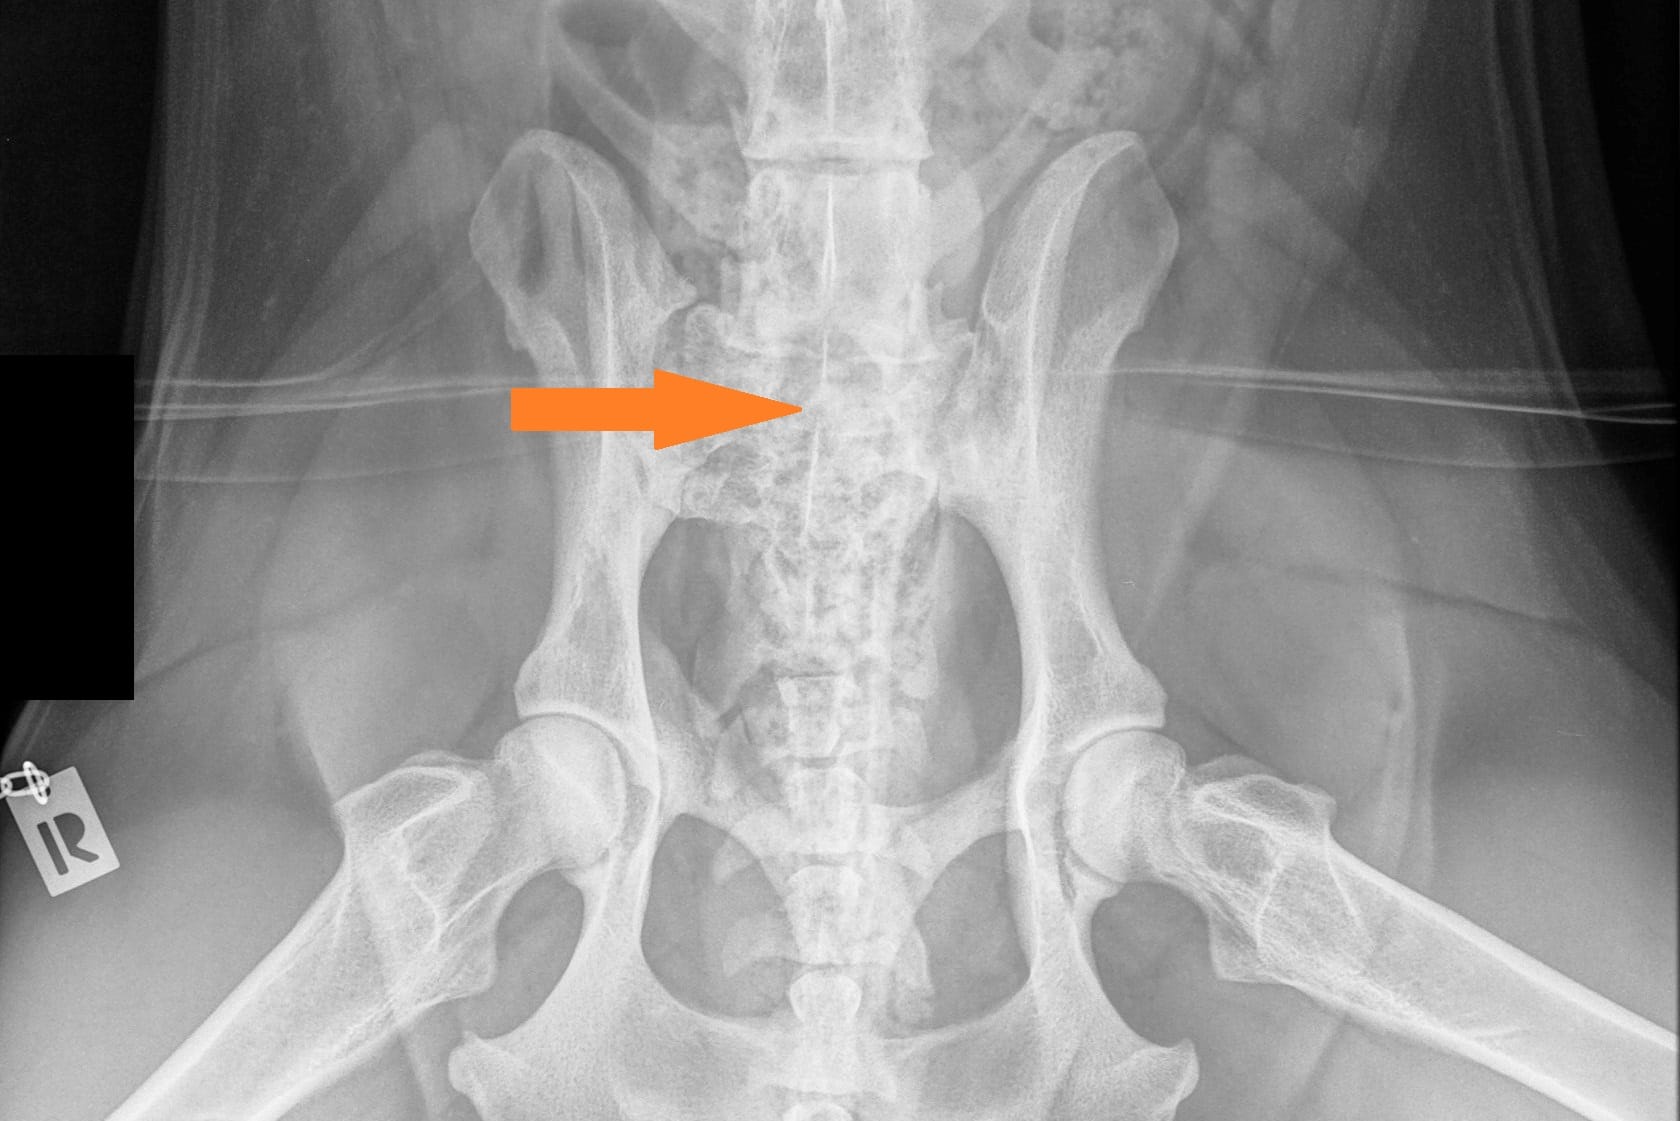

LTV4; 8 lannenikamaa. L8 on puhdas lannenikama ja siinä on normaalit okahaarakkeet.

Toiseksi suurin osuus on 22,9% LTV4 (6/8 lannenikamaa). Useimmilla näistä lannenikamia on 8 (lumbarisaatio).